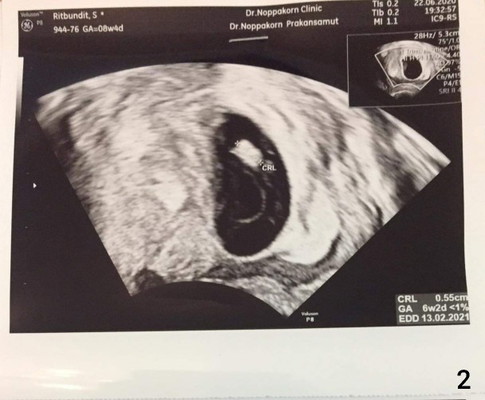

พึ่งไปซาวมาเมื่อวานค่ะ พบตัวน้องอายุได้ 6 สัปดาห์ 2 วัน แต่ยังไม่เห็นหัวใจ เราจะให้เห็นห้วใจตอนกี่วีคค่ะ ปล.ถ้านับจากวันที่ประจำเดือนล่าสุดมาอายุครรภ์คือ 8 สัปดาห์ แต่คุณหมอบอกว่าไข่เราตกช้า ไป2 สัปดาห์ค่ะ